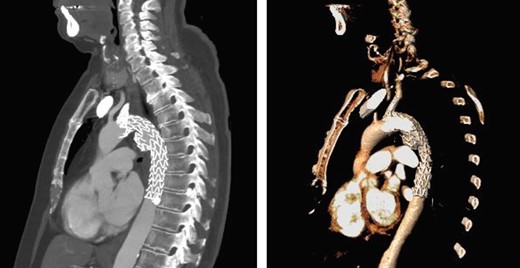

A 74-year-old woman was referred to our vascular service with a 6-month history of hoarseness of voice and intermittent dry cough. The patient’s medical history included hypertension and gastroesophageal reflux disease. Flexible laryngoscopy demonstrated a foreshortened, lateralised and flaccid vocal fold consistent with unilateral vocal cord paralysis. Subsequent computed tomography (CT) imaging of the neck and thorax revealed a saccular aneurysm in the aortopulmonary window measuring 39 mm (Fig. 1). Digital subtraction angiography confirmed the presence of a ductal aneurysm with a well-defined neck and no intraluminal thrombus (Fig. 2). There was no contrast extravasation into the mediastinum or pulmonary circulation. Following a cardiovascular multidisciplinary meeting, treatment options were discussed with the patient and consensus favoured endovascular repair. The distance from the proximal margin of the aneurysmal neck to the origin of the left subclavian artery measured just under 2 cm and therefore did not meet the manufacturer’s minimal landing zone requirements. To circumnavigate this dilemma, a left subclavian stent graft was inserted with its proximal end parallel to the main thoracic endoprosthesis. The procedure was uncomplicated and repeat imaging revealed widely patent stent grafts with satisfactory positioning and absence of endoleak (Fig. 3). Our patient was discharged home on the second postoperative day. She continued speech and language therapy postoperatively and has made remarkable recovery of phonation, declining any further treatment options for same.

Sagittal CT with 3D reconstruction demonstrated a 39-mm saccular aneurysm along the lesser curvature of the aortic arch, expanding in the direction of the pulmonary artery.